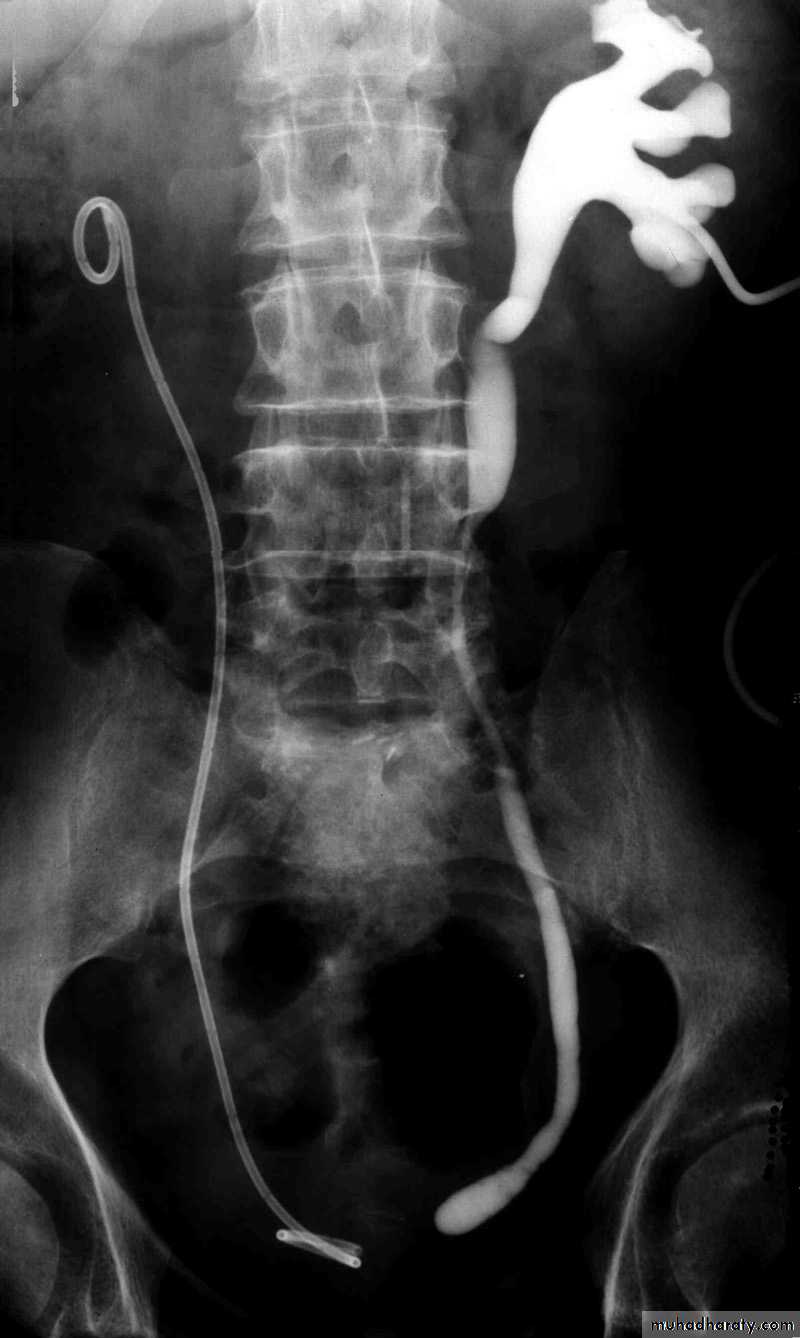

Postcaval (Retrocaval) ureter (Preureteral Vena Cava )

The right ureter pass behind the inferior vena cava

This might causes obstruction

Vascular abnormality

Incidence: about 1 in 1500Although it is congenital, most patients present at 3rd or 4th decade.

Diagnosis: IVU

Treatment:

surgical correction involves ureteral division, with relocation and ureteroureteral or ureteropelvic reanastomosis,

usually with excision or bypass of the retrocaval segment, which can

be aperistaltic